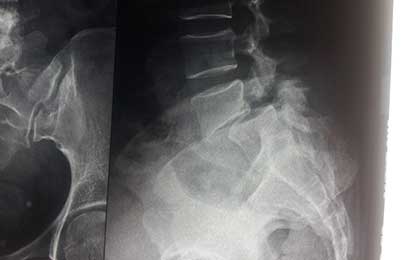

L5 S1 DEG LYSIS LISTHESIS

pre op xray 1